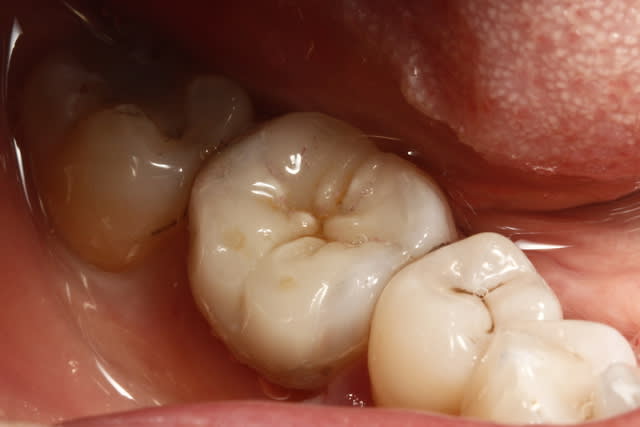

Emax sans retouche (mais effectivement le prothésiste devrait savoir que les crêtes se mettent à la même hauteur) , inséré à la "main" et carie occlusale ...)))

pour rester dans les onlay... un gros :)

un cas de ce matin.

-avec, IDS (immediate dentin sealing) très pratique pour avoir une étanchéité le jour de la préparation, aurais pu/du se faire sous digue....

- Collage avec composite de stratification chauffé et vibré, très facile pour gérer les excès ...

- Permettra de comparer le vieillissement de l'onlay versus composite direct ...